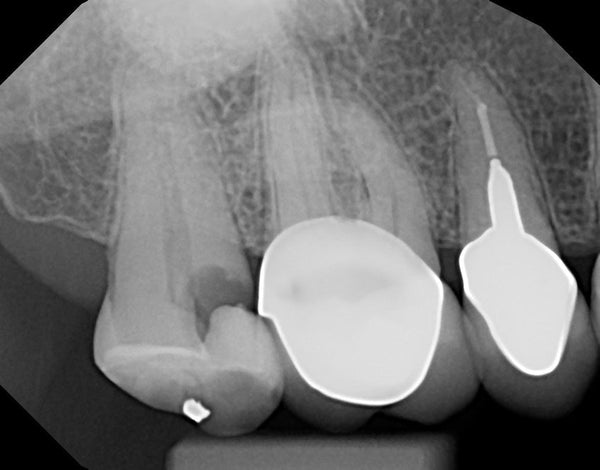

Dahl technique Doc Terry style by Dr. Ahmad Fayad

Introduction: 40 year old female on a tight budget and is slowly losing her teeth. She was referred to me by another patient who had the same style buildups. Decided... Read More